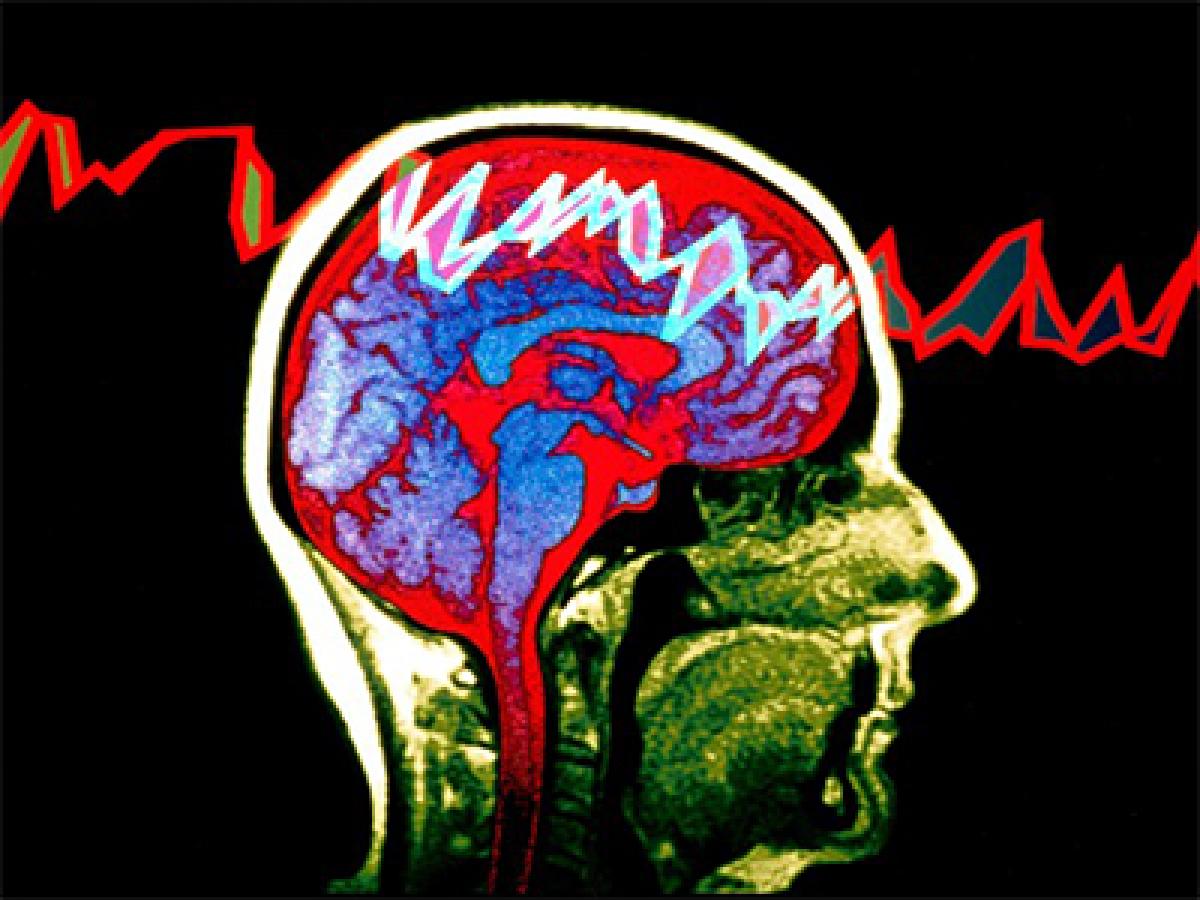

The researchers compared the musical processing abilities of the brains of people with and without epilepsy using an electroencephalogram, where electrodes are attached to the scalp to detect and record brain wave patterns. They collected data from 21 patients who were in the epilepsy monitoring unit at a US medical centre between September 2012 and May 2014.

The researchers found significantly higher levels of brain wave activity in participants when they were listening to music. More importantly brain wave activity in people with epilepsy tended to synchronize more with the music, especially in the temporal lobe, than in people without epilepsy, Charyton said. Charyton said this research suggests music might be a novel intervention to help people with epilepsy. The research was presented at the American Psychological Association's 123rd annual convention in Toronto.